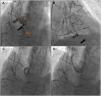

After discussion with the hospital's heart team and risk-benefit assessment, we decided that the surgical risk of reoperation was high and the patient was proposed for percutaneous closure. The procedure was performed under local anesthesia, with two arterial accesses (right radial 5F and femoral 6F) and one venous access for introduction of the ICE probe (right femoral vein, 8F). The ICE probe (ACUSON AcuNav ultrasound catheter, Siemens, Mountain View, CA) was placed in the right ventricle with optimal visualization and alignment with the fistula (Figure 2A). A 5F pigtail catheter was positioned in the ascending aorta, and the fistula's position was confirmed by angiography (Figure 3A). A 5F MP1 catheter was advanced through the right femoral artery, crossing the fistula into the right ventricle (Figures 2B and 3B). Through the MP1 an 0.035“Amplatzer guidewire was positioned in the right ventricle and the 5F diagnostic MP1 was exchanged for a 6F MP1 guiding catheter. The percutaneous closure device, a 6 mm Amplatzer Vascular Plug II (AVP) (Abbott, Chicago, IL), was then implanted (Figures 2C and 3C). ICE confirmed the correct positioning of the device, with minimal residual flow, and excluded interference with neighboring structures (Figures 2D and 3D). There were no complications regarding this procedure and the patient was discharged on the following day. At nine-month follow-up the patient is doing well, without heart failure or other complaints.

Fluoroscopic guidance of aorto-RV fistula closure. (A) Identification of aorto-RV fistula by aortography using a 5F pigtail catheter; (B) 6F MP1 catheter passing across the defect and an 0.035” Amplatzer guidewire positioned in the right ventricle; (C) 6 mm Amplatzer Vascular Plug II positioned; (D) after device deployment, no residual shunt was observed on angiography. Ao: aorta; RV: right ventricle.